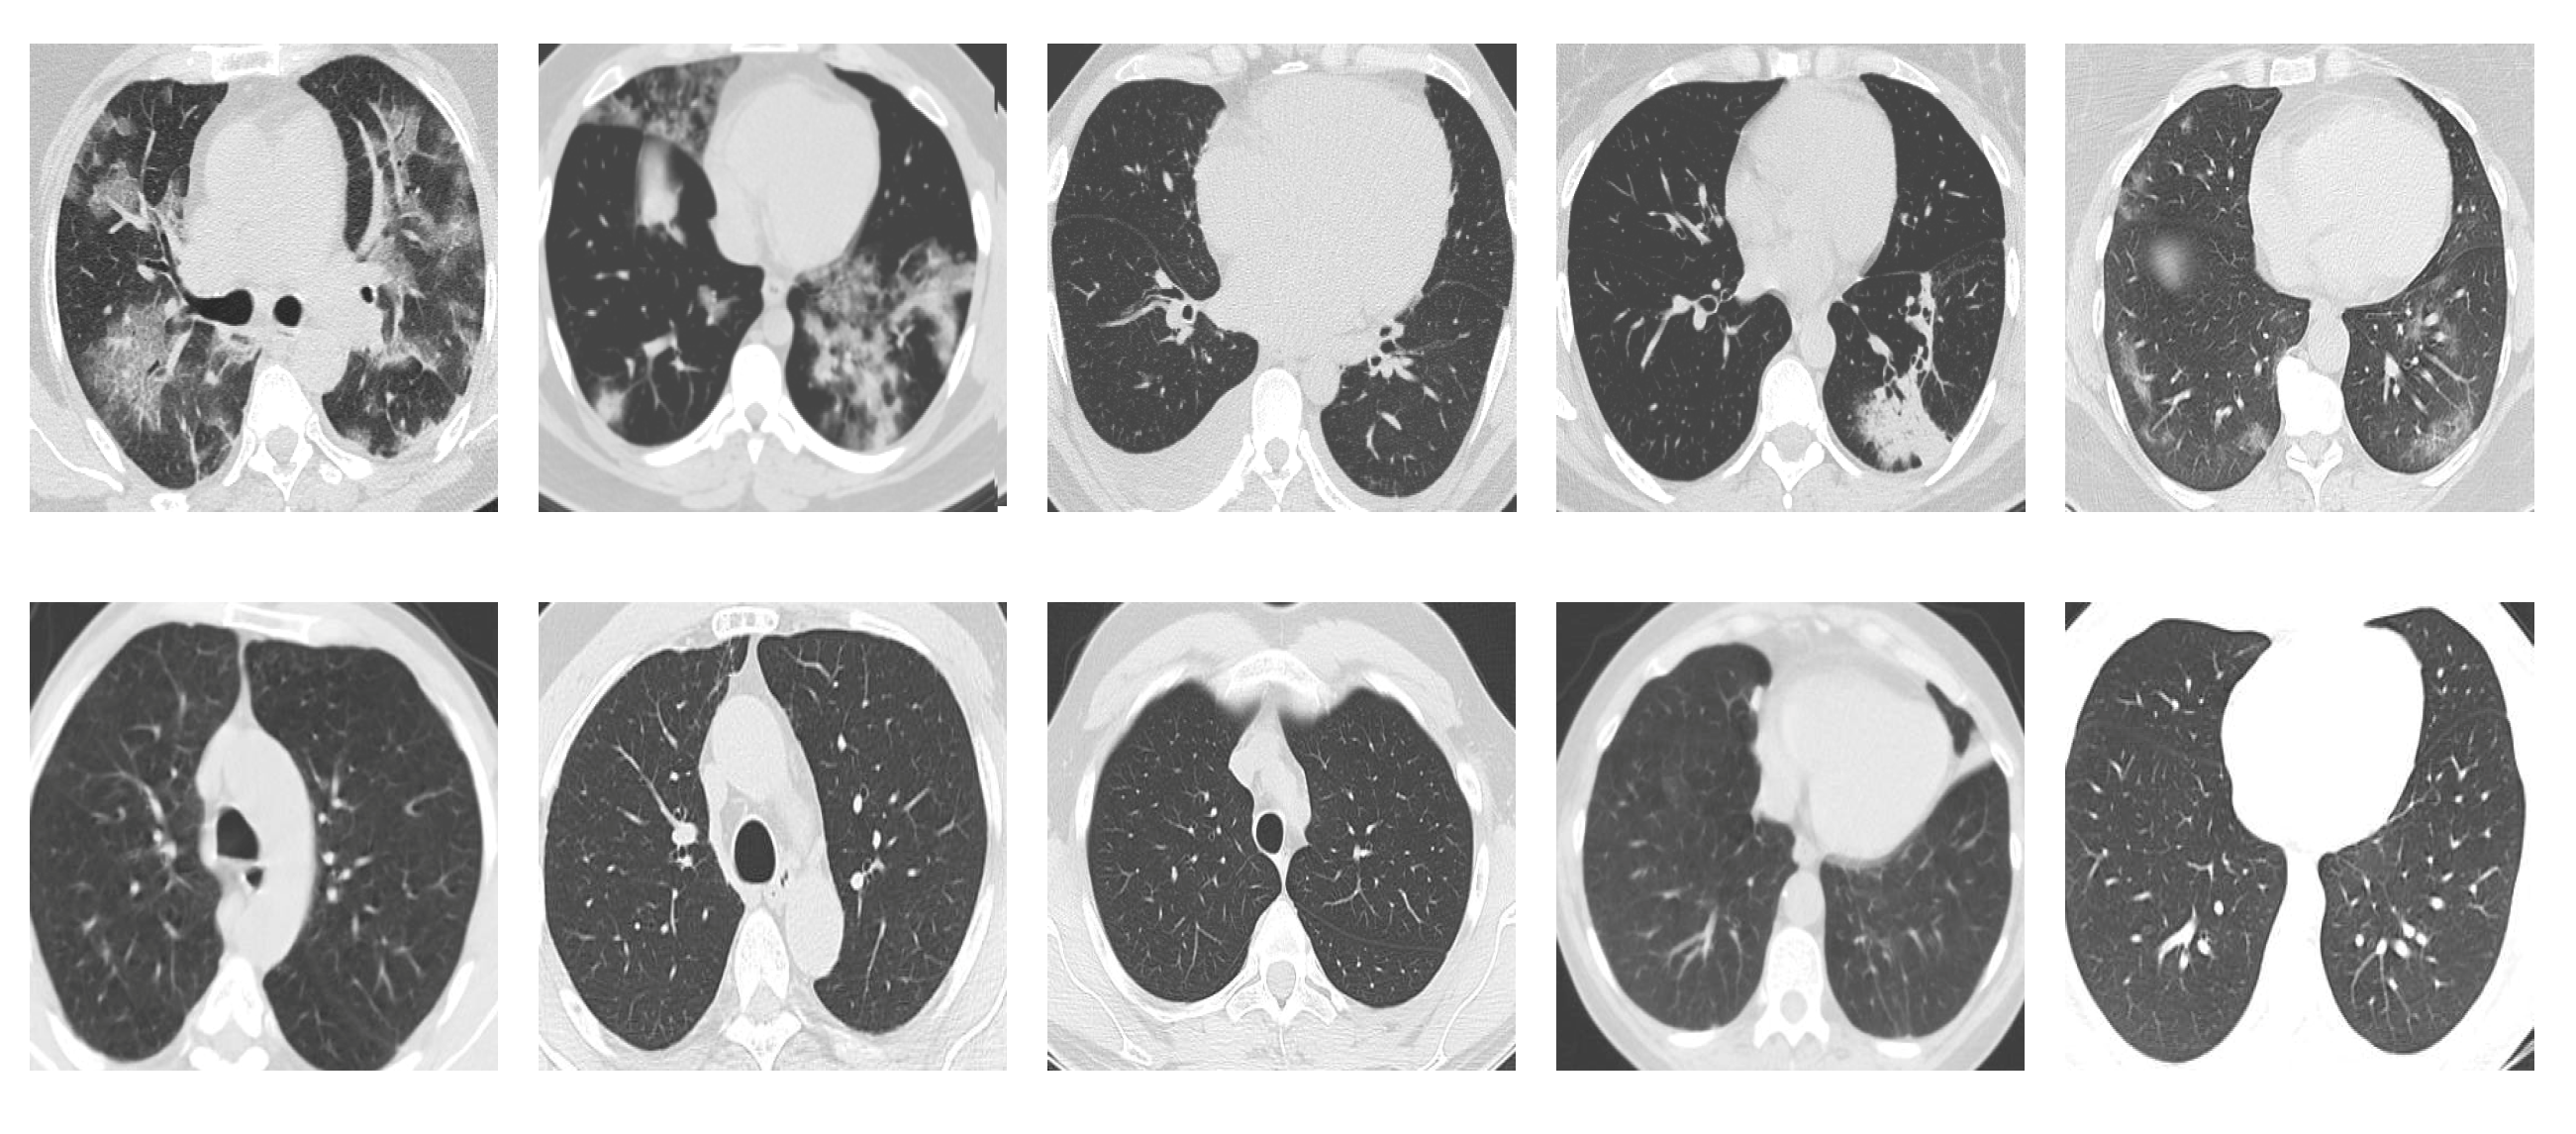

SARS-CoV-2 CT Scan dataset [53]: The dataset was collected from hospitals of Sao Paulo, Brazil, with a total of 2482 CT scans acquired from 120 patients of both genders. It is composed of 1252 scans for patients infected with SARS-CoV-2, and 1230 scans for patients infected with other lung diseases. The CT scans have varying spatial sizes between and , and are available in PNG format. CT scans from this dataset are shown in Figure 7.

Figure 7.

Examples of chest CT scans from the SARS-CoV-2 CT dataset. The first row represents CT scans diagnosed with COVID-19, whereas the second row represents non-COVID-19.

COVID19-CT dataset [54]: The dataset consists totally of 746 CT images. There are 349 CT images of patients with COVID-19 and 397 CT images showing non-COVID-19, but other pulmonary diseases. The positive CT images were collected from preprints about COVID-19 on medRxiv and bioRxiv, and they feature various manifestations of COVID-19. Since the CT images were taken from different sources, they have varying sizes between and . Figure 8 shows example CT images from the COVID19-CT dataset.

Figure 8.

Examples of chest CT images from the COVID19-CT dataset. The first row represents CT images diagnosed with COVID-19, whereas the second row represents non-COVID-19 cases, but other lung diseases.